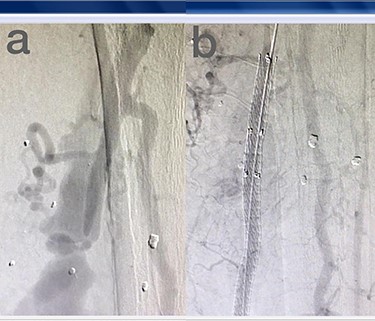

Sites of injury included 6 Posterior Tibialis arteries (27.2%) (Fig. 1), 2 deep femoral arteries (9.09%), 2 Superficial femoral arteries (9.09%) and 2 maxillary arteries (9.09%). We had only one injured artery (4.54%) in each of the following sites: internal pudendal a., Axillary a. (Fig. 2), Proneal a., Lumbar a., External carotid a., Anterior Tibialis a., common iliac a. (Fig. 3), temporal a., Thoracic aorta and Internal iliac artery (Fig. 4).

(a) Posterior Tibialis artery before intervention, (b) after endovascular stent graft deployment.